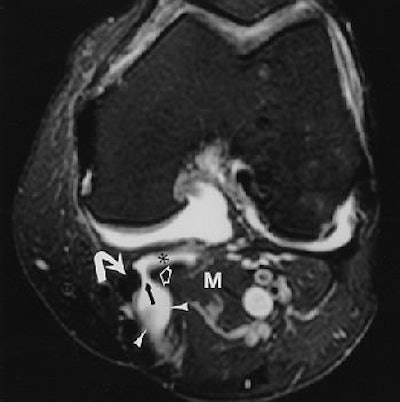

![]() |

| Same patient as above. Axial proton density-weighted MR image with fat saturation reveals Baker's cyst (arrowheads) with fluid (black arrow) between semimembranosus tendon (curved white arrow) and medial gastrocnemius (open arrow). Note subgastrocnemius component (asterisk) of Baker's cyst. M = medial gastrocnemius muscle. Ward EE, Jacobson JA, Fessell DP, Hayes CW, and van Holsbeeck M, "Sonographic Detection of Baker's Cysts Comparison with MR Imaging" (AJR 2001; 176:373-380). |